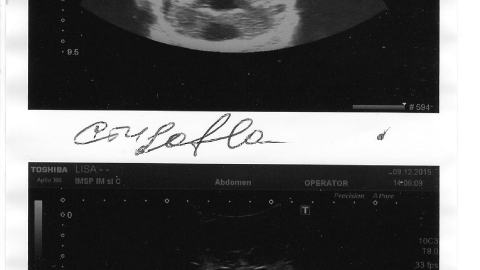

Артём родился 09.11.2015. При первичном обследовании врачи обнаружили большой спектр врождённых пороков сердца. Сейчас Артём находится в отделении патологии Центра Матери и Ребёнка, однако он нуждается в серии операций в Киевском кардиологическом центре и лечении составляет свыше 20 000 евро.